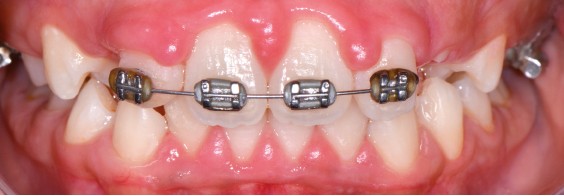

Ainsi, lors des périodes de désordres hormonaux, comme la puberté, la grossesse et la ménopause, on observe fréquemment des inflammations exacerbées qui peuvent révéler une susceptibilité de l’hôte aux maladies parodontales. (fig. 2 et 3).

Souvent, les signes cliniques régressent spontanément lorsque…